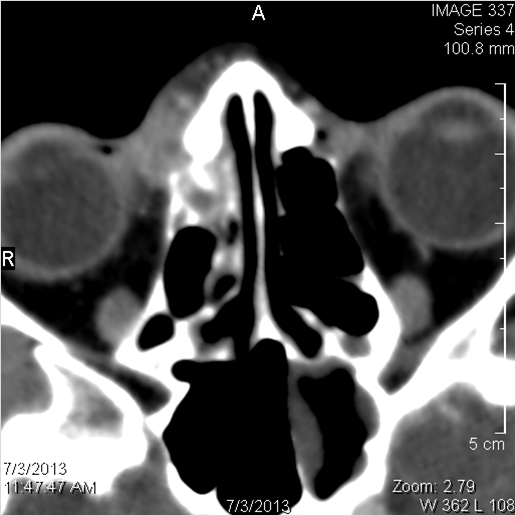

22 year old male presenting earlier on this date to the emergency room with frontal headaches, fever and intracranial complications of acute sinusitis. Now admitted to the neurosurgery service.Exam

Findings are consistent with the clinical diagnosis of acute or subacute frontal sinusitis with intracranial complications with extensive epidural empyema as well as subdural empyema the latter spreading within the falx to the tentorium with evidence of localized cerebritis and meningitis involving the right frontal lobe.